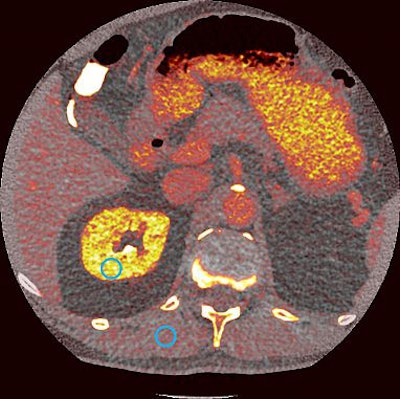

The imaging provided by photon-counting CT will allows clinicians to identify materials such as iodine with great anatomic precision, the agency said. The new technology may help characterize tumors, plaques, and vessels smaller than 0.5 mm, as well as identify soft tissues such as tendons or collagen, which are hard to differentiate with current equipment.